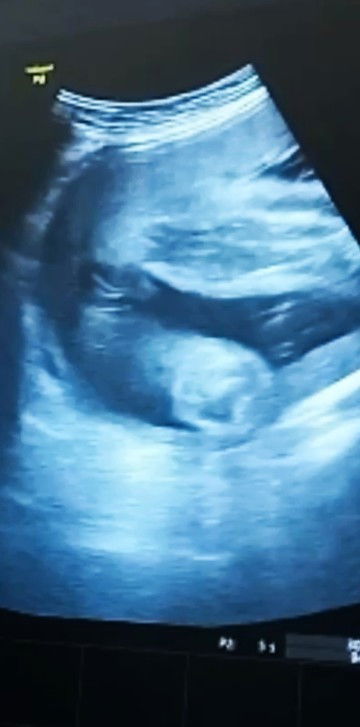

here is my ultrasound ❤️ and my ob gyn said the gender is female but I see it as a boy. what do you think ? Respect post. Tia🫶 #Gender #babygirlorboy #Teamfeb